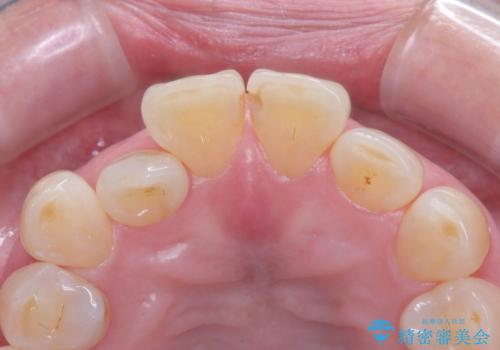

- 前歯の隙間とへこみが気になり、特に舌で触ると気になってストレスを感じるとのことで来院された患者様です。

上下ともに軽度の叢生があり、下顎がやや前突傾向にあったため、本来であれば矯正治療が第一選択となります。矯正によって下の前歯を後方に移動させることで、咬み合わせの改善とともに前歯のデコボコも整えることができます。

しかし、患者様はワイヤー矯正もマウスピース矯正も「絶対にしたくない」との強いご希望がありました。